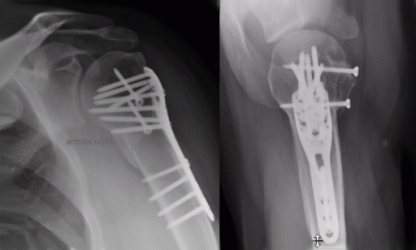

The operation is performed under a combination of general and regional anaesthesia. The fracture is exposed, the bone fragments realigned and then fixed with a plate and screws or other device such as an intramedullary nail. The fixation may occasionally be supplemented with bone grafting using “off the shelf” bone substitutes or augmented using bone cement.

Before

After